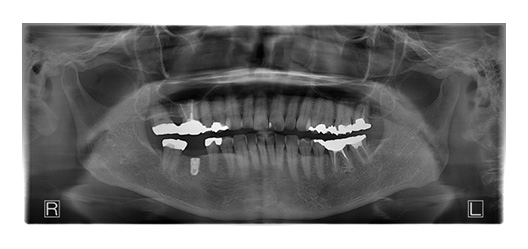

CASE_01

70代男性(インプラント)

- 患者さん情報(年齢・性別)

- 70代 男性

- 主訴

- 歯を失ってしまったところにインプラントに入れたい

- 治療箇所

- 7箇所

- 治療方法

- インプラント

- 費用

- 約320万円

- 治療期間

- 約1年

- その治療によるリスク・副作用

-

- 治療期間がながい、外科的治療が必要

- 患者様の声